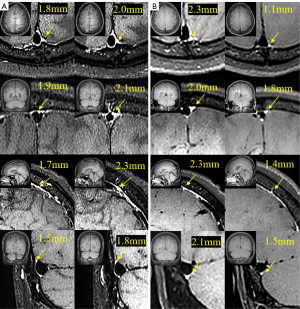

Both contrast agent-enhanced and nonenhanced BB images with the same layer thickness geometry (acquisition interval ≤30 s) were acquired, with mLVs being hyperintensive only in the enhanced BB sequences. Three blinded neuroradiologists (each with ≥6 years of experience) independently used workstation calipers (A site, 0.1 mm) to measure the largest mLV diameter within 3 cm of the superior sagittal sinus (SSS) in the most conspicuous slice identified on axial, coronal, and sagittal images; the procedure was repeated bilaterally for the transverse sinus (TS) (Figure 2). For each lesion, the thickest perisinus mLV within 10 mm of the tumor margin was similarly measured, which served as the regional mLV diameter (Figure S1). Each observer repeated the measurements after a 2-week interval to determine the intraclass correlation coefficient (ICC), with an ICC ≥0.90 indicating reproducibility. The primary outcome was favorable treatment response (FTR), defined as stable disease (SD) or partial response (PR) at 6 months after therapy initiation, assessed according to immune Response Evaluation Criteria in Solid Tumors (iRECIST). Progressive disease (PD) was considered an unfavorable outcome (Figure 3).

Figure 2 The process of mLV measurement in the BM and non-BM groups. (A) mLV measurements with the BB sequence in a patient without BMs. (B) mLV measurement with the BB sequence in a patient with BMs. The yellow arrows in the figure indicate the thickest points of the mLV. BB, black-blood; BM, brain metastasis; mLV, meningeal lymphatic vessel.

Figure 3 Typical example from each of the SD + PR group and the PD group. (A) Comparison of mLV diameter measurements before and after treatment in a patient with brain metastases in the PD group. (B) Comparison of mLV diameter measurements before and after treatment in a patient with brain metastases in the PR group. The yellow arrows in the figure indicate the thickest points of the mLV. mLV, meningeal lymphatic vessel; PD, progressive disease; PR, partial response; SD, stable disease.